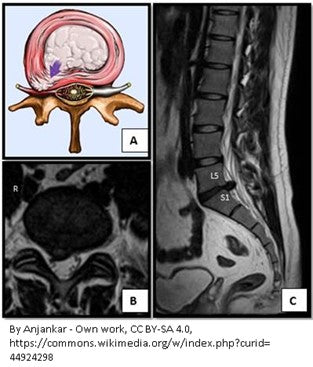

90% of Herniated Discs Occur at L4-L5 & L5-S1

L4-L5 Herniated Disc Could Cause:

- Sciatica pain

- Weakness when raising the big toe

- Possible weakness in the ankle (aka as “foot drop”)

- Numbness and pain on top of the foot

L5-S1 Herniated Disc Could Cause:

- Weakness when standing on the toes

- Numbness and pain can radiate down into the sole of the foot and the outside of the foot